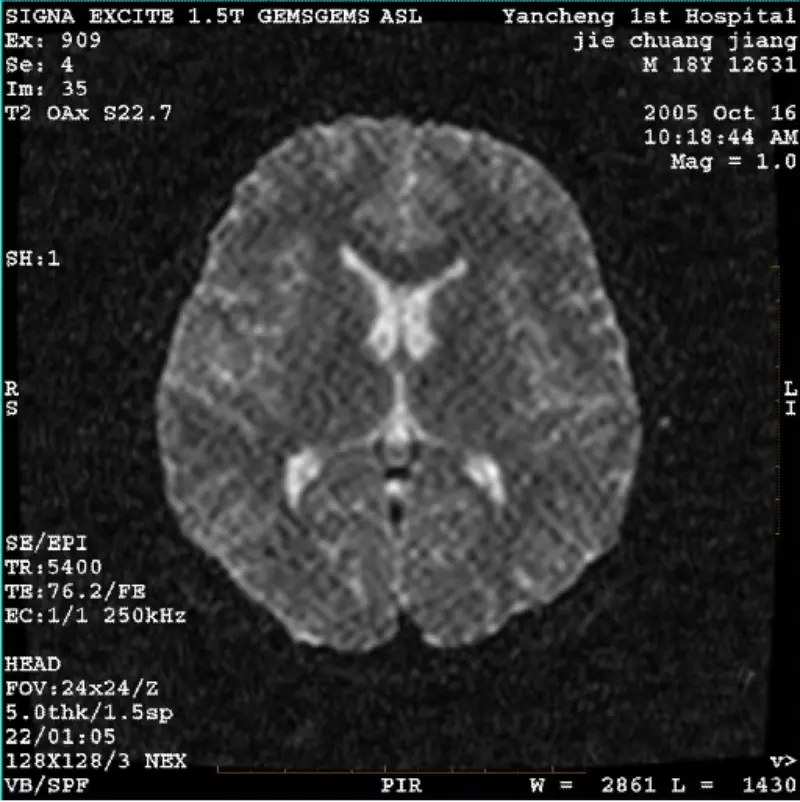

WeiterlesenSYSTEM: 1.5T Signa Twin Excite II (Softwareversion 11.0M4) PROBLEM/SYMPTO DWI- (Zoom-Modus und Gesamtmodus) und Fiesta-Bild (Zoom-Modus und Gesamtmodus). Sichtbare Netz- oder Kordartefakte, unabhängig davon, ob Körperspule oder Kopf verwendet werden Spule, andere Routinebilder scheinen normal......